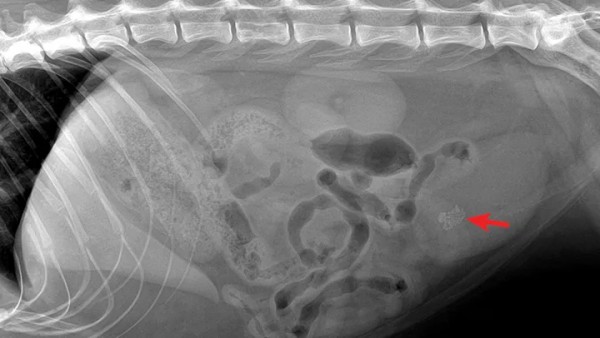

04【诊断标准】 1.根据病史及体格检查做出诊断。有无撞伤、摔伤史。 2.超声检查:可见膀胱内有膀胱黏膜及内部回声的变化,也可见低回声的团块,有游离性。 3.膀胱破裂在超声下可见腹腔有积液,(穿刺取样确诊是否为尿液)。 4.腹腔尿液的检查:腹腔积液做尿素,肌酐,血容比,总蛋白量及细胞学检查。若腹水中的肌酐高于血液中的肌酐,则可确定为尿液。 5.X线检查:膀胱逆行造影,检查有无膀胱破裂。